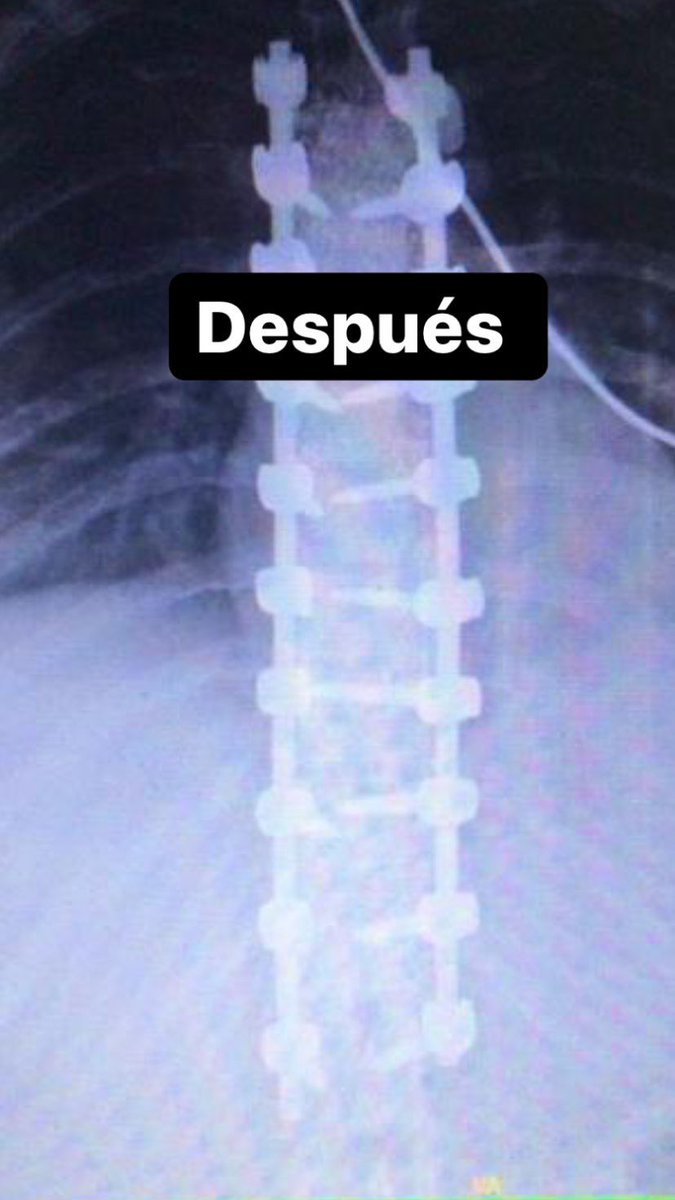

Me la hice 👍🏻 Es tan terrible como parece

Bilim Dünyası@dunyasalbilim

Skolyoz nasıl düzeltilir?